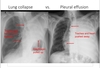

Not at all

2

3

Q

PE?

A

• PE: pain more often pleuritic